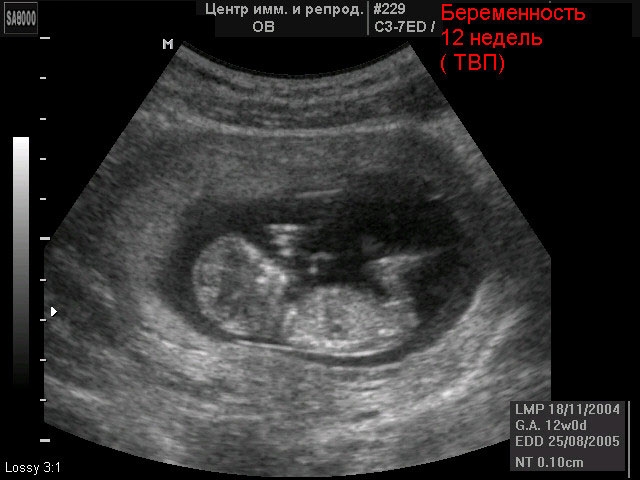

Ultrasound of the fetus at 12 weeks of gestation

During an ultrasound, you can clearly see how the fetus looks. Already without any decoding and explanation of the doctor, one can distinguish the contours of the body. The baby's body is slightly larger than his head, and the arms and legs are barely distinguishable - they are still very short and thin. In very rare cases, modern equipment will allow the doctor to recognize the sex of the child - provided that the crotch of the baby is clearly visible. On standard diagnosticians, this information will not be available for a long time.

If you have not registered, go to the doctor. For a period of 11-13 weeks, it is time to conduct a so-called screening. This is a comprehensive examination. On ultrasound, the doctor will check some specific parameters of the fetus. For example, it will evaluate the size of the occipital region, according to which the threat of Down syndrome is determined in the early stages. Blood tests for certain hormones will reveal various malformations of the fetus, if any.